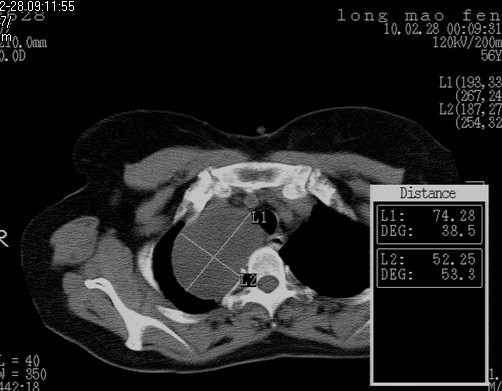

以下是引用随光逐影在2010-3-1 8:36:00的发言:[br]右上纵隔囊性占位性病变,考虑支气管囊肿,不排除神经源性肿瘤。